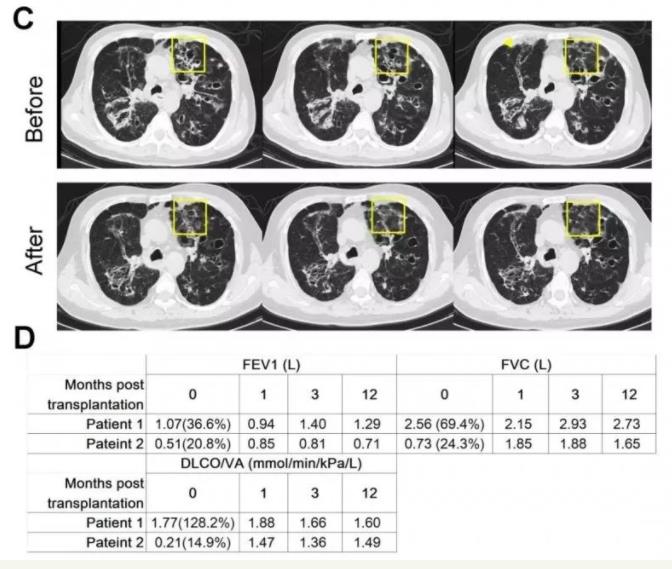

《蛋白質(zhì)與細(xì)胞》雜志以封面文章形式發(fā)表了同濟(jì)大學(xué)醫(yī)學(xué)院左為教授團(tuán)隊(duì)重大突破成果??蒲腥藛T從患者支氣管取出干細(xì)胞,體外擴(kuò)增后移植至患者肺部病灶部位;3至6個(gè)月后,這些干細(xì)胞形成了新的肺泡和支氣管結(jié)構(gòu),完成了對(duì)患者肺部損傷組織的修復(fù)替代。

目前左為團(tuán)隊(duì)一共開展了超過80例臨床肺干細(xì)胞移植,這些患者的肺功能,特別是肺的彌散功能有比較明顯的改善。

肺功能檢測(cè)提示,移植干細(xì)胞三個(gè)月之后各項(xiàng)肺功能開始出現(xiàn)好轉(zhuǎn)并保持到一年之后